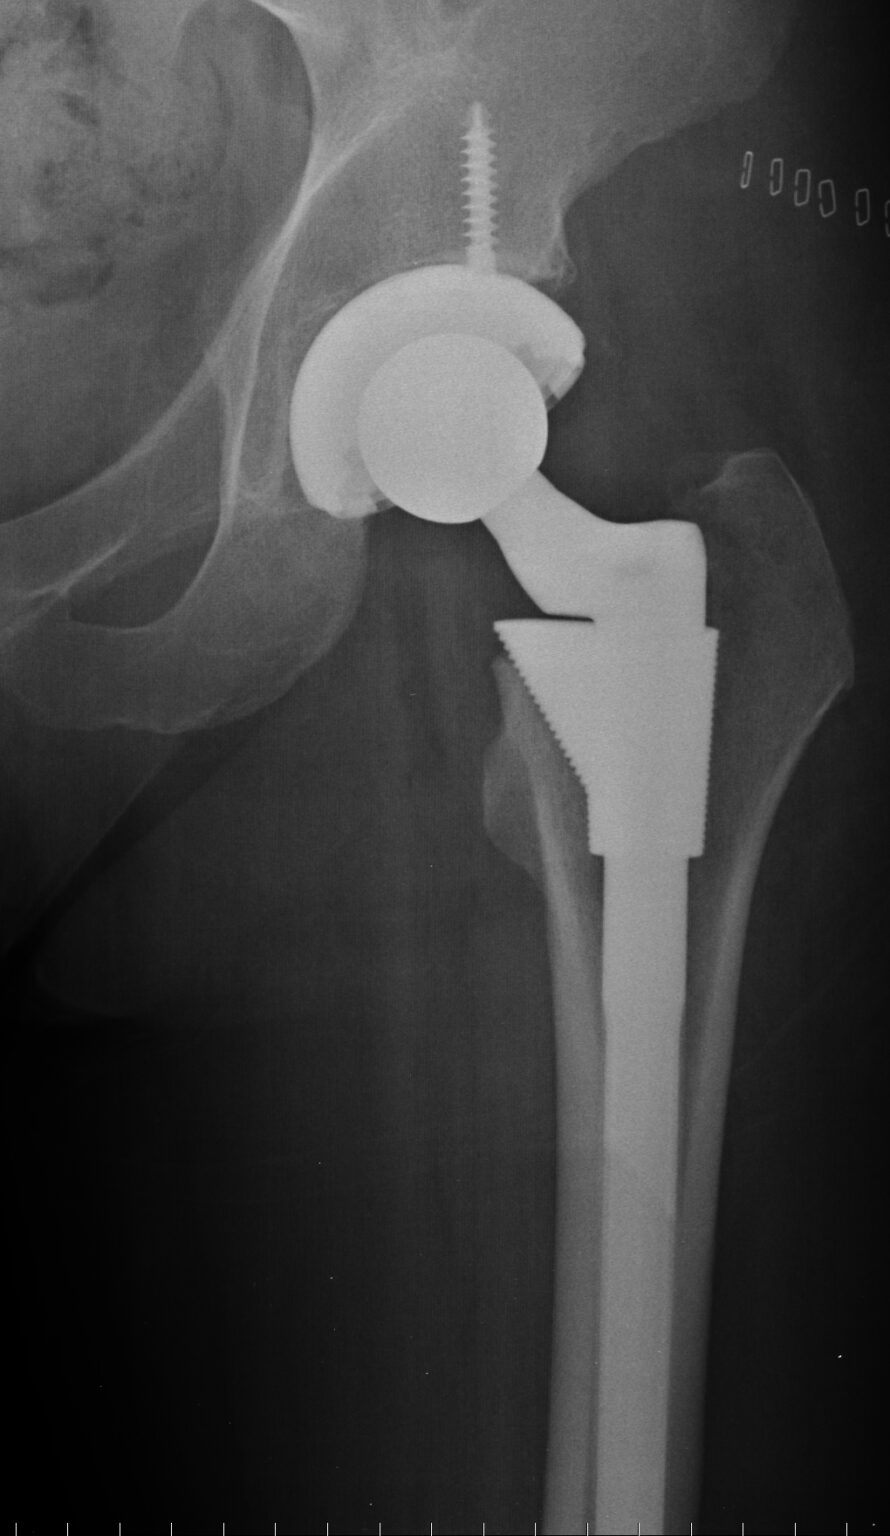

Total Hip Replacement Hip Osteoarthritis Hip Replacement Recovery Issues    health and wellness. “on average, hip replacement recovery can take around two to four weeks, but everyone is different,” says thakkar. Published on 18 oct 2021.   full recovery from a hip replacement varies from person to person, but most people are doing well three months after the surgery.  how long does it take to recover after a. Hip Replacement Recovery Issues.